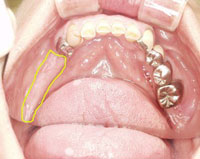

下の写真をご覧下さい。(写真1)

この写真は、先日当院でのインプラント治療を行った50代女性の口腔内写真です。左の黄色い部分で囲っている部分が骨ですが、骨の幅は十分にあります。

次の写真をご覧下さい。(写真2)

同じく当院でインプラント手術をされた50代女性の口腔内写真です。

3本の歯を失い、その部分をインプラント埋入された患者さまです。

右側の黄色く囲っている部分が骨です。

先ほどの写真1の方に比べると骨幅が半分以下の厚みしかありません。

骨の幅に十分に厚みがある方のインプラント手術は、それほど困難ではないはずです。つまり6ミリの木の棒に4ミリの釘を入れることは可能です。

しかし、このように骨が非常に薄く、骨量が少ない方の手術は、いわゆる「難症例」といい、執刀するドクターの技術の高さによって成功するかどうかが決定すると言われている症例です。

つまり2ミリの木の棒に4ミリの釘を入れることは単純に考えれば棒が折れるので、不可能ということです。